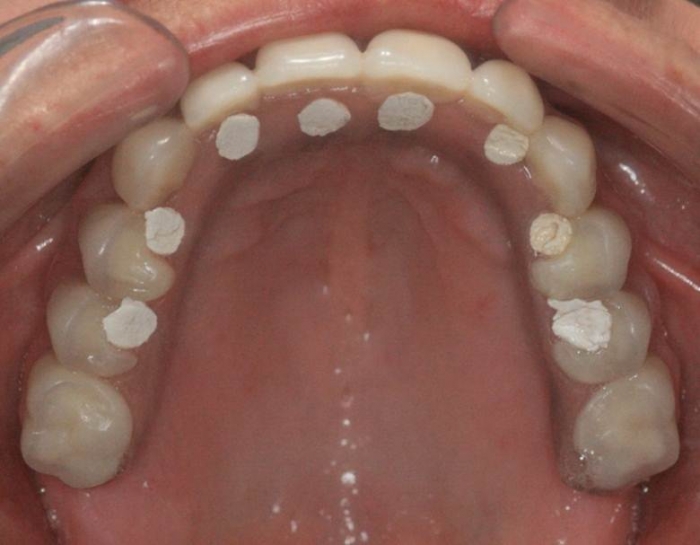

Prótese fixa em resina sobre implantes, restaurada provisoriamente